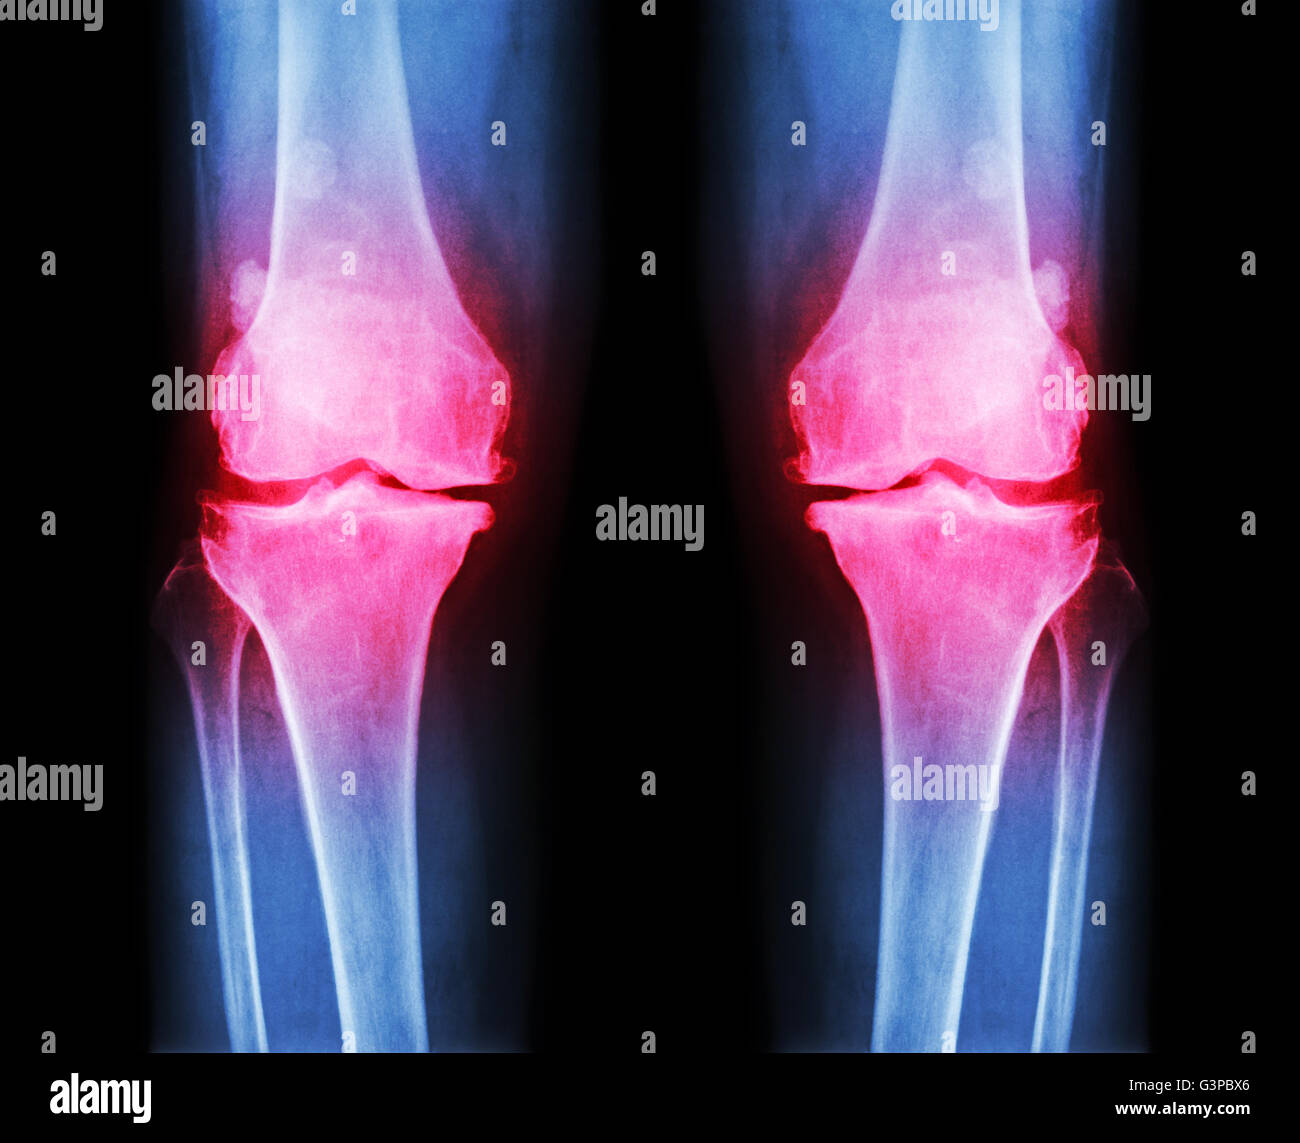

L'arthrose du genou les . film x-ray ( AP ) postérieure antérieure - de montrer l'espace étroit du genou mixte , ( ) , épi ostéophyte subco Banque D'Imageshttps://www.alamyimages.fr/image-license-details/?v=1https://www.alamyimages.fr/photo-image-l-arthrose-du-genou-les-film-x-ray-ap-posterieure-anterieure-de-montrer-l-espace-etroit-du-genou-mixte-epi-osteophyte-subco-105598478.html

L'arthrose du genou les . film x-ray ( AP ) postérieure antérieure - de montrer l'espace étroit du genou mixte , ( ) , épi ostéophyte subco Banque D'Imageshttps://www.alamyimages.fr/image-license-details/?v=1https://www.alamyimages.fr/photo-image-l-arthrose-du-genou-les-film-x-ray-ap-posterieure-anterieure-de-montrer-l-espace-etroit-du-genou-mixte-epi-osteophyte-subco-105598478.htmlRFG3PBX6–L'arthrose du genou les . film x-ray ( AP ) postérieure antérieure - de montrer l'espace étroit du genou mixte , ( ) , épi ostéophyte subco

L'arthrose du genou les . film x-ray ( AP ) postérieure antérieure - de montrer l'espace étroit du genou mixte , ( ) , épi ostéophyte subco Banque D'Imageshttps://www.alamyimages.fr/image-license-details/?v=1https://www.alamyimages.fr/photo-image-l-arthrose-du-genou-les-film-x-ray-ap-posterieure-anterieure-de-montrer-l-espace-etroit-du-genou-mixte-epi-osteophyte-subco-105598486.html

L'arthrose du genou les . film x-ray ( AP ) postérieure antérieure - de montrer l'espace étroit du genou mixte , ( ) , épi ostéophyte subco Banque D'Imageshttps://www.alamyimages.fr/image-license-details/?v=1https://www.alamyimages.fr/photo-image-l-arthrose-du-genou-les-film-x-ray-ap-posterieure-anterieure-de-montrer-l-espace-etroit-du-genou-mixte-epi-osteophyte-subco-105598486.htmlRFG3PBXE–L'arthrose du genou les . film x-ray ( AP ) postérieure antérieure - de montrer l'espace étroit du genou mixte , ( ) , épi ostéophyte subco

L'arthrose du genou les . film x-ray ( AP ) postérieure antérieure - de montrer l'espace étroit du genou mixte , ( ) , épi ostéophyte subco Banque D'Imageshttps://www.alamyimages.fr/image-license-details/?v=1https://www.alamyimages.fr/photo-image-l-arthrose-du-genou-les-film-x-ray-ap-posterieure-anterieure-de-montrer-l-espace-etroit-du-genou-mixte-epi-osteophyte-subco-105598501.html

L'arthrose du genou les . film x-ray ( AP ) postérieure antérieure - de montrer l'espace étroit du genou mixte , ( ) , épi ostéophyte subco Banque D'Imageshttps://www.alamyimages.fr/image-license-details/?v=1https://www.alamyimages.fr/photo-image-l-arthrose-du-genou-les-film-x-ray-ap-posterieure-anterieure-de-montrer-l-espace-etroit-du-genou-mixte-epi-osteophyte-subco-105598501.htmlRFG3PBY1–L'arthrose du genou les . film x-ray ( AP ) postérieure antérieure - de montrer l'espace étroit du genou mixte , ( ) , épi ostéophyte subco

L'arthrose du genou les . film x-ray ( AP ) postérieure antérieure - de montrer l'espace étroit du genou mixte , ( ) , épi ostéophyte subco Banque D'Imageshttps://www.alamyimages.fr/image-license-details/?v=1https://www.alamyimages.fr/photo-image-l-arthrose-du-genou-les-film-x-ray-ap-posterieure-anterieure-de-montrer-l-espace-etroit-du-genou-mixte-epi-osteophyte-subco-105598460.html

L'arthrose du genou les . film x-ray ( AP ) postérieure antérieure - de montrer l'espace étroit du genou mixte , ( ) , épi ostéophyte subco Banque D'Imageshttps://www.alamyimages.fr/image-license-details/?v=1https://www.alamyimages.fr/photo-image-l-arthrose-du-genou-les-film-x-ray-ap-posterieure-anterieure-de-montrer-l-espace-etroit-du-genou-mixte-epi-osteophyte-subco-105598460.htmlRFG3PBWG–L'arthrose du genou les . film x-ray ( AP ) postérieure antérieure - de montrer l'espace étroit du genou mixte , ( ) , épi ostéophyte subco

L'ARTHROSE DU GENOU Arthrose du genou ( ). Film x-ray deux genou ( vue avant ) show spatial commun étroit ( perte de cartilage ) , osteophy Banque D'Imageshttps://www.alamyimages.fr/image-license-details/?v=1https://www.alamyimages.fr/photo-image-l-arthrose-du-genou-arthrose-du-genou-film-x-ray-deux-genou-vue-avant-show-spatial-commun-etroit-perte-de-cartilage-osteophy-87802628.html

L'ARTHROSE DU GENOU Arthrose du genou ( ). Film x-ray deux genou ( vue avant ) show spatial commun étroit ( perte de cartilage ) , osteophy Banque D'Imageshttps://www.alamyimages.fr/image-license-details/?v=1https://www.alamyimages.fr/photo-image-l-arthrose-du-genou-arthrose-du-genou-film-x-ray-deux-genou-vue-avant-show-spatial-commun-etroit-perte-de-cartilage-osteophy-87802628.htmlRFF2RN44–L'ARTHROSE DU GENOU Arthrose du genou ( ). Film x-ray deux genou ( vue avant ) show spatial commun étroit ( perte de cartilage ) , osteophy

L'ARTHROSE DU GENOU Arthrose du genou ( ). Film x-ray deux genou ( vue avant ) show spatial commun étroit ( perte de cartilage ) , osteophy Banque D'Imageshttps://www.alamyimages.fr/image-license-details/?v=1https://www.alamyimages.fr/photo-image-l-arthrose-du-genou-arthrose-du-genou-film-x-ray-deux-genou-vue-avant-show-spatial-commun-etroit-perte-de-cartilage-osteophy-87802655.html

L'ARTHROSE DU GENOU Arthrose du genou ( ). Film x-ray deux genou ( vue avant ) show spatial commun étroit ( perte de cartilage ) , osteophy Banque D'Imageshttps://www.alamyimages.fr/image-license-details/?v=1https://www.alamyimages.fr/photo-image-l-arthrose-du-genou-arthrose-du-genou-film-x-ray-deux-genou-vue-avant-show-spatial-commun-etroit-perte-de-cartilage-osteophy-87802655.htmlRFF2RN53–L'ARTHROSE DU GENOU Arthrose du genou ( ). Film x-ray deux genou ( vue avant ) show spatial commun étroit ( perte de cartilage ) , osteophy

L'ARTHROSE DU GENOU Arthrose du genou ( ). Film x-ray deux genou ( vue avant ) show spatial commun étroit ( perte de cartilage ) , osteophy Banque D'Imageshttps://www.alamyimages.fr/image-license-details/?v=1https://www.alamyimages.fr/photo-image-l-arthrose-du-genou-arthrose-du-genou-film-x-ray-deux-genou-vue-avant-show-spatial-commun-etroit-perte-de-cartilage-osteophy-87802612.html

L'ARTHROSE DU GENOU Arthrose du genou ( ). Film x-ray deux genou ( vue avant ) show spatial commun étroit ( perte de cartilage ) , osteophy Banque D'Imageshttps://www.alamyimages.fr/image-license-details/?v=1https://www.alamyimages.fr/photo-image-l-arthrose-du-genou-arthrose-du-genou-film-x-ray-deux-genou-vue-avant-show-spatial-commun-etroit-perte-de-cartilage-osteophy-87802612.htmlRFF2RN3G–L'ARTHROSE DU GENOU Arthrose du genou ( ). Film x-ray deux genou ( vue avant ) show spatial commun étroit ( perte de cartilage ) , osteophy

L'ARTHROSE DU GENOU Arthrose du genou ( ). Film x-ray deux genou ( vue avant ) show spatial commun étroit ( perte de cartilage ) , osteophy Banque D'Imageshttps://www.alamyimages.fr/image-license-details/?v=1https://www.alamyimages.fr/photo-image-l-arthrose-du-genou-arthrose-du-genou-film-x-ray-deux-genou-vue-avant-show-spatial-commun-etroit-perte-de-cartilage-osteophy-87802643.html

L'ARTHROSE DU GENOU Arthrose du genou ( ). Film x-ray deux genou ( vue avant ) show spatial commun étroit ( perte de cartilage ) , osteophy Banque D'Imageshttps://www.alamyimages.fr/image-license-details/?v=1https://www.alamyimages.fr/photo-image-l-arthrose-du-genou-arthrose-du-genou-film-x-ray-deux-genou-vue-avant-show-spatial-commun-etroit-perte-de-cartilage-osteophy-87802643.htmlRFF2RN4K–L'ARTHROSE DU GENOU Arthrose du genou ( ). Film x-ray deux genou ( vue avant ) show spatial commun étroit ( perte de cartilage ) , osteophy